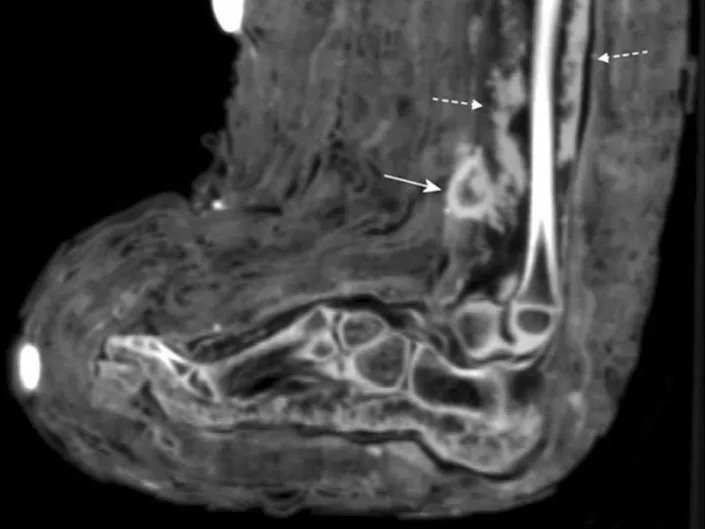

In this case, Zink said, the bandages were spotted while the scientists carried out routine CT scans of mummies, as can be seen in the scans below and annotated with the full-lined arrow.

The wound appeared to have been infected when she died, as the scans showed signs of “pus,” Zink said. These signs of infection are marked by the dotted arrows in the scans below.